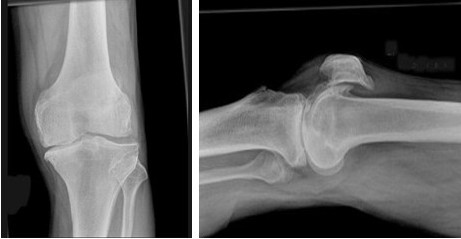

男,76岁,长久站立时左膝关节疼痛,可扪及捏发音,结合图像,最可能的诊断是( )

A、退行性骨关节病

B、畸形性骨炎

C、神经性关节病

D、创伤性关节炎

E、肥大性骨关节病

男,76岁,左膝关节长久站立时疼痛,可捫及捏发音,请结合图像,选出最可能的诊断